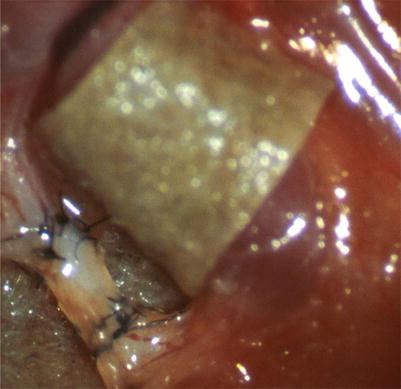

On the contrary, the reaction around the absorbable sutures diminished with time after the operation. Just remnants of the material were seen as contents of foreign body giant cells (Fig. 2.10).

Fig. 2.10

Patent anastomosis of the abdominal thoracic duct, absorbable suture material polyglactin 910, 6 weeks after surgery, minor foreign body reaction (H-E, tenfold magnification of objective)

In summary, the diameter of the foreign body reaction of the nonabsorbable material was bigger than the lymphatic vessel diameter itself. Therefore we used absorbable material further on. Polyglactin 910 was available with a size of 11-0 until the process of production was altered. Nowadays only the size 10-0 is available.